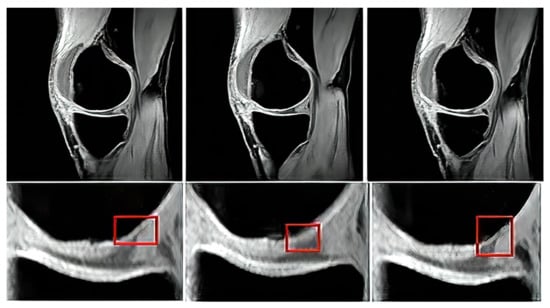

Proton density sequence plays an indispensable role in structural investigation of the early stage of articular cartilage loss. Here, only a weak contrast between a common cartilage surface and such pathological findings are notable. Therefore, for our analysis these data are substantially important. To objectivize such findings, we provide the example (Figure 5) from our dataset, where such investigations can be observed.

Based on the reported analysis of the segmentation performance, mostly the combination of fuzzy thresholding with the ABC evolutionary algorithms appeared as the best segmentation strategy, judging by reported objectivization parameters and mainly provided statistical tests of significance. In this subsection, we would like to provide the last analysis of selected features extraction of articular cartilage from MR images based on the fuzzy thresholding with the ABC algorithm. The aim of this analysis is firstly computing a multiregional segmentation model, allowing for a decomposition of the MR image into a finite number (in this case five) segmentation regions. Consequently, a region, representing the articular cartilage, is selected (Figure 20) as the region of interest, while the rest of the segmentation regions are suppressed from the segmentation model (Figure 20). By this selection scheme, we obtain a binary segmentation model, exclusively classifying the articular cartilage from the rest of the tissues in the MR images. Figure 20 also presents a multiregional segmentation of a part of articular cartilage (femoral cartilage) affected by osteoarthritis of I. grade, which is notable by two segmented lobes of the articular cartilage, and between them is a gap, where the cartilage is missing. To objectize the quality of the articular cartilage extraction and the preciseness of the reported features, we extracted the same features for the gold standard manual segmentation of articular cartilage. Consequently, the feature differences are compared to quantify the segmentation effectivity of articular cartilage detection. Note that we used the following settings for the ABC algorithm: 100 iterations and population size 50. The following cartilage features are considered for evaluation:

Figure 20. Example of segmentation results for articular cartilage and its features extraction based on fuzzy thresholding with ABC optimization: (a) gold standards by manual annotation, (b) binary segmentation, (c) native MR image with area of interest indicated by the green square (top) and multiregional segmentation with 4 regions (bottom), where yellow contours reflect two lobes of articular cartilage from region of interest, and (d) binary extraction of articular cartilage fused with the gold standard (red contour).